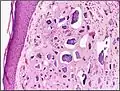

| Micrograph of calcinosis cutis. The calcification is purple (bottom of image). H&E stain. | |